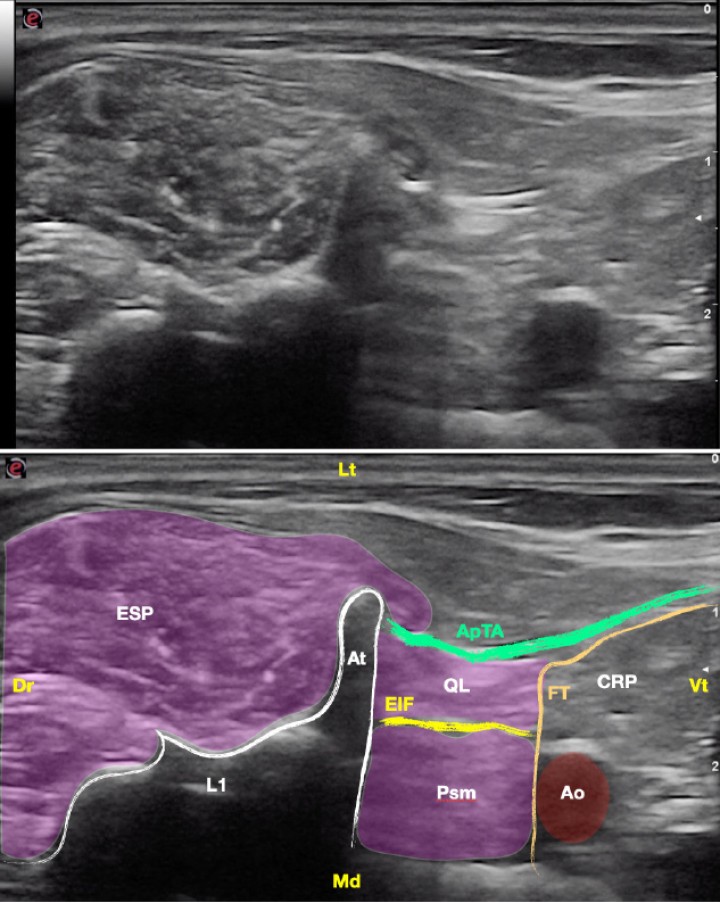

<p>Imagen ecográfica del músculo cuadrado lumbar. Músculo cuadrado lumbar (QL), músculo psoas menor (Psm), espacio interfascial (EIF), aponeurosis de inserción del músculo transverso abdominal (ApTA), fascia transversalis (FT), cavidad retroperitoneal (CRP), arteria aorta (Ao), grupo del erector espinal (ESP), vértebra L1 (L1), apófisis transversa (At). Dr: Dorsal, Vt: Ventral, Lt: Lateral, Md: Medial.</p>

Figura 13

Imagen ecográfica del músculo cuadrado lumbar. Músculo cuadrado lumbar (QL), músculo psoas menor (Psm), espacio interfascial (EIF), aponeurosis de inserción del músculo transverso abdominal (ApTA), fascia transversalis (FT), cavidad retroperitoneal (CRP), arteria aorta (Ao), grupo del erector espinal (ESP), vértebra L1 (L1), apófisis transversa (At). Dr: Dorsal, Vt: Ventral, Lt: Lateral, Md: Medial.

<p>(<strong>A</strong>) Posición del transductor y la aguja para el abordaje en plano del músculo cuadrado lumbar. (<strong>B</strong>) Imagen esquemática de las estructuras anatómicas y la aguja. Músculo cuadrado lumbar (QL), músculo psoas menor (Psm), espacio interfascial (EIF), aponeurosis de inserción del músculo transverso abdominal (ApTA), fascia transversalis (FT), cavidad retroperitoneal (CRP), arteria aorta (Ao), grupo del erector espinal (ESP), vértebra L1 (L1), apófisis transversa (At). Dr: Dorsal, Vt: Ventral, Lt: Lateral, Md: Medial.</p>

Figura 17

(A) Posición del transductor y la aguja para el abordaje en plano del músculo cuadrado lumbar. (B) Imagen esquemática de las estructuras anatómicas y la aguja. Músculo cuadrado lumbar (QL), músculo psoas menor (Psm), espacio interfascial (EIF), aponeurosis de inserción del músculo transverso abdominal (ApTA), fascia transversalis (FT), cavidad retroperitoneal (CRP), arteria aorta (Ao), grupo del erector espinal (ESP), vértebra L1 (L1), apófisis transversa (At). Dr: Dorsal, Vt: Ventral, Lt: Lateral, Md: Medial.